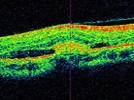

Perhaps the most commonplace piece of technology in an ophthalmologist’s office, optical coherence tomography provides information on both the optic nerve RNFL and macula. Functioning like an ultrasound device, except that light waves are used instead of sound, it provides high resolution imaging of the eye. Multiple companies manufacture OCT devices, including Carl Zeiss (Cirrus HD-OCT), Topcon (3D OCT-2000), Optovue (RTVue-100), and Optos (Spectral OCT/SLO). These all have pros and cons that may make one device preferable for one practice and a different device for another. It is important to note that the RTVue-100 is fourier-domain OCT while the spectral and 3D OCT-2000 are spectral-domain OCT. Additionally, the Spectral and HD-OCT (4000 model) combine SLO with OCT imaging. All of these devices are designed to integrate well with electronic medical record systems.